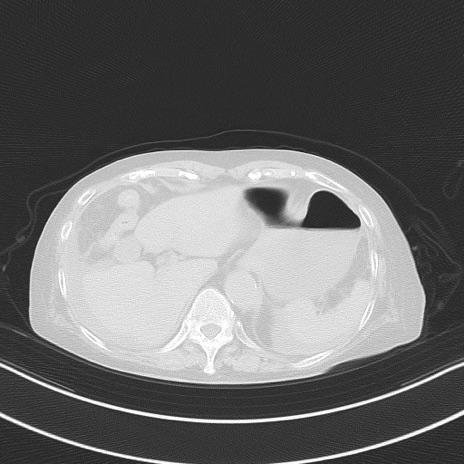

症例40(横断像)他院1日前

横断像

他院CT